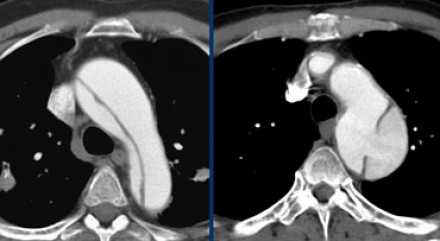

![11]()

- Слева представлен пациент со Stanford A. Диссекция с четкой визуализируемой интимой.

- Справа представлен пациент со Stanford B. Патология локализована в нисходящей аорте. «Точка входа» расположена ниже уровня левой подключичной артерии.